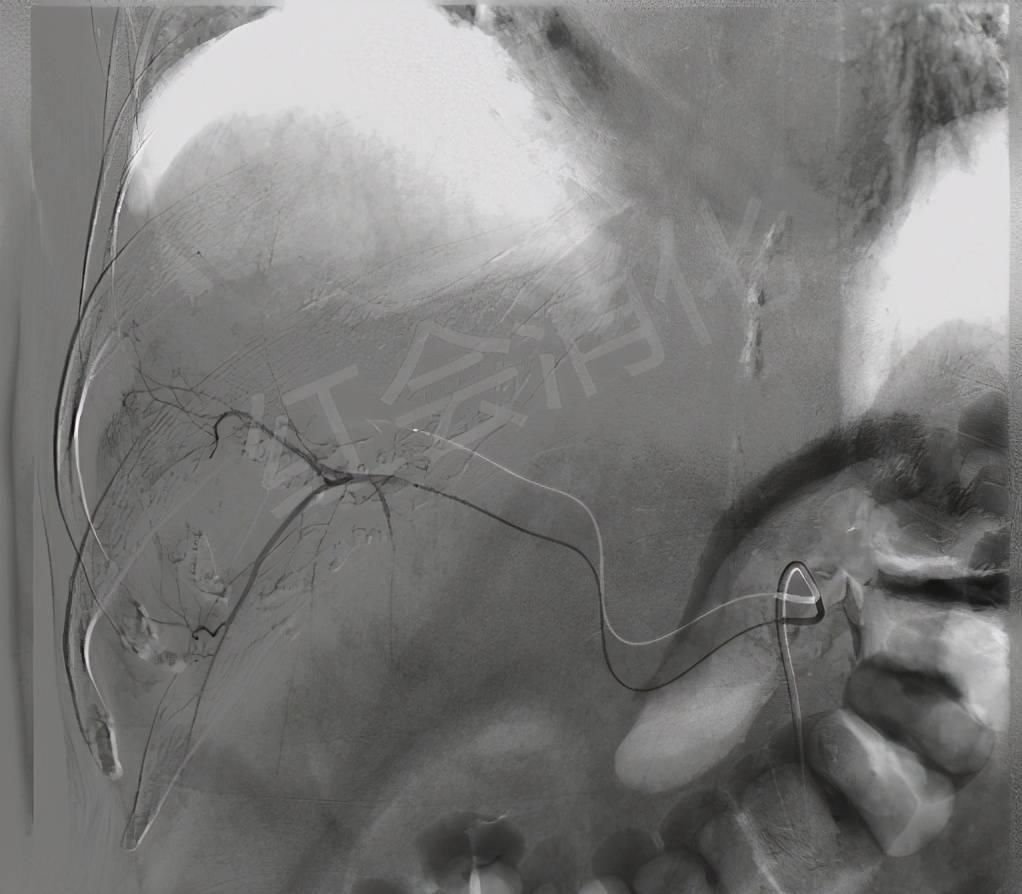

栓塞前造影

文章图片

超选后造影